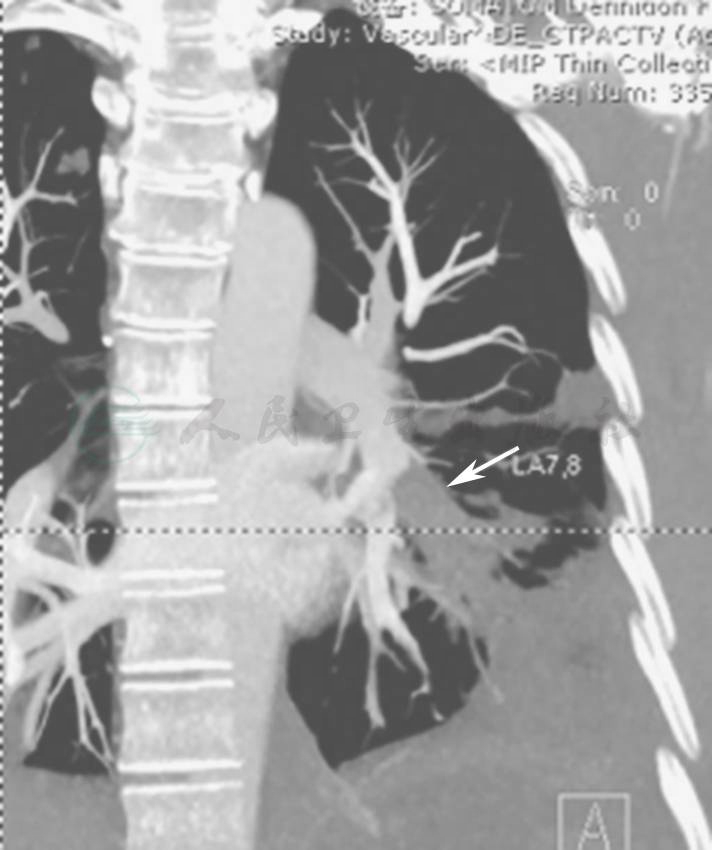

胸部CT+CTPA+CTV(2011年9月1日):多发肺动脉栓塞;双肺结节、空洞、大片渗出影较前(2011年8月18日)有明显吸收,双侧胸腔积液也有所吸收(图3~图5);未见明确深静脉血栓形成。

图4 CTPA表现(2011-09-01)

CTPA显示左下叶内前段肺动脉栓塞,伴左侧胸腔积液

图5 CTPA表现(2011-09-01)

CTPA显示右下叶外后段肺动脉栓塞,伴后肋膈角少量胸腔积液